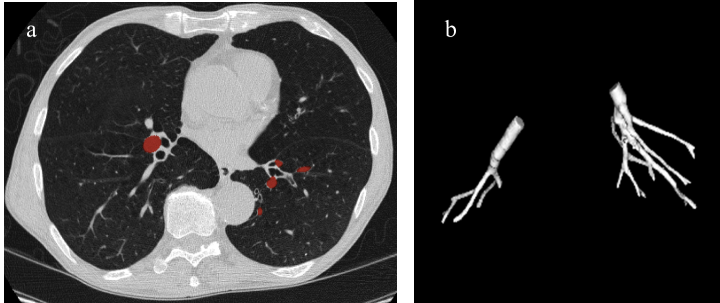

The airways and pulmonary arteries run parallel and adjacent to each other in units known as bronchopulmonary segments. This symmetry provides the key for our automated pulmonary artery seed point detector. The airway lumen is automatically segmented and labelled using a region-growing method with an automatically generated seed point in the trachea [15]. Using the segmented airway, a curved cylindrical region of interest is constructed around individual airway branches to limit the search space for the pulmonary arteries. A cubic spline S(n)𝑆𝑛S(n) is fit to the airway, and the scan is resampled to construct cutting planes orthogonal to the spline, spaced at constant intervals. Figure 2a diagrams the processes of generating the 3D ROI, and shows a single frame for illustration.

Refer to captionRefer to captionmissing-subexpression\begin{array}[]{cc}\includegraphics[width=383.03122pt]{PaperSeed.pdf}\end{array}

Figure 2: a) Diagram of the airway ROI construction process and a single frame from the output. b) Progressive morphological opening operation to isolate the pulmonary artery. c) Complete process diagram for the identification of seed points within the pulmonary artery.

The algorithm for locating the pulmonary arteries within the reconstructed ROI is outlined in Figure 2c. The ROI is thresholded at -400 HU, and the soft tissue structures are separated using a 3D morphological opening operation to separate the heart from the pulmonary arteries (Figure 2b). The resulting objects are labeled with a 3D connected component algorithm.

Each unique object is then checked to see if it is a possible candidate for the pulmonary artery. Objects which extend past 4 cm from the center of the airway contain areas of the heart and are eliminated. Of the remaining objects after the elimination, the component that is closest to the airway center is identified as the pulmonary artery, as predicted by the bronchopulmonary model. If no components are found, the morphological operation opening was too small to isolate the artery. In this case, the size of the kernel is increased by one voxel and the process is repeated until the pulmonary artery is identified.

The location of the isolated pulmonary artery is then defined as the centroid of the artery, in the ROI frame most proximal to the heart. This ensures that vessel tracking begins as close to the start of the vessel as possible, increasing the extent of the segmentation. The orientation of the artery was found by computing the centroid of the artery in the most distal frame it appears in the ROI, and taking the vector from the proximal centroid to the distal centroid as the initial artery orientation.